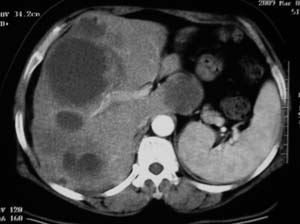

以下是引用余辉在2009-3-12 8:36:00的发言:[br]肝内多发囊性病变,部分囊内有单发或多发\"子囊\"表现,囊壁均较光整,多考虑多发包虫感染.[br]但本例做了增强,原平扫病灶高密度区有延迟强化(不知是不是对比错觉,建议提供具本对比ct值),如果真有强化的话应该是转移瘤了

以下是引用dyqct在2009-3-12 7:52:00的发言:[br]肝内多发性占位,转移性囊性癌可能大。支持!